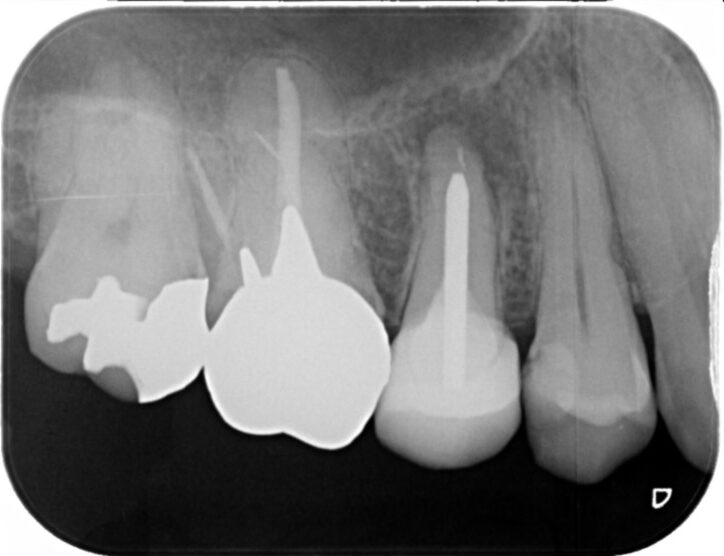

40代 男性

術前ですが左下6に大きな病変を認め膿がたまり抜歯が必要であるといわれ当院にお見えになりました。

根管治療術後2年です。膿の袋は綺麗に消失し被せ物が入り特に問題のない状態です。

費用 | 100000円 |

治療期間 | 6か月 |

注意事項(リスク・副作用など) | 治療の刺激や薬剤の刺激により、治療後数時間から数日後に痛みや腫れが生じる場合があります。 |

カテゴリ | 歯内療法 |